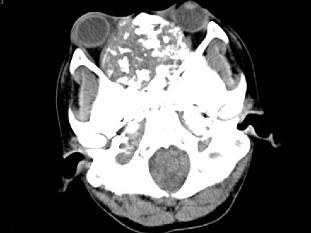

男,26岁,进行性鼻腔阻塞、流涕来院就诊,近两年持续性头痛、头晕,如图所示筛窦区占位灶应诊断为 ( )